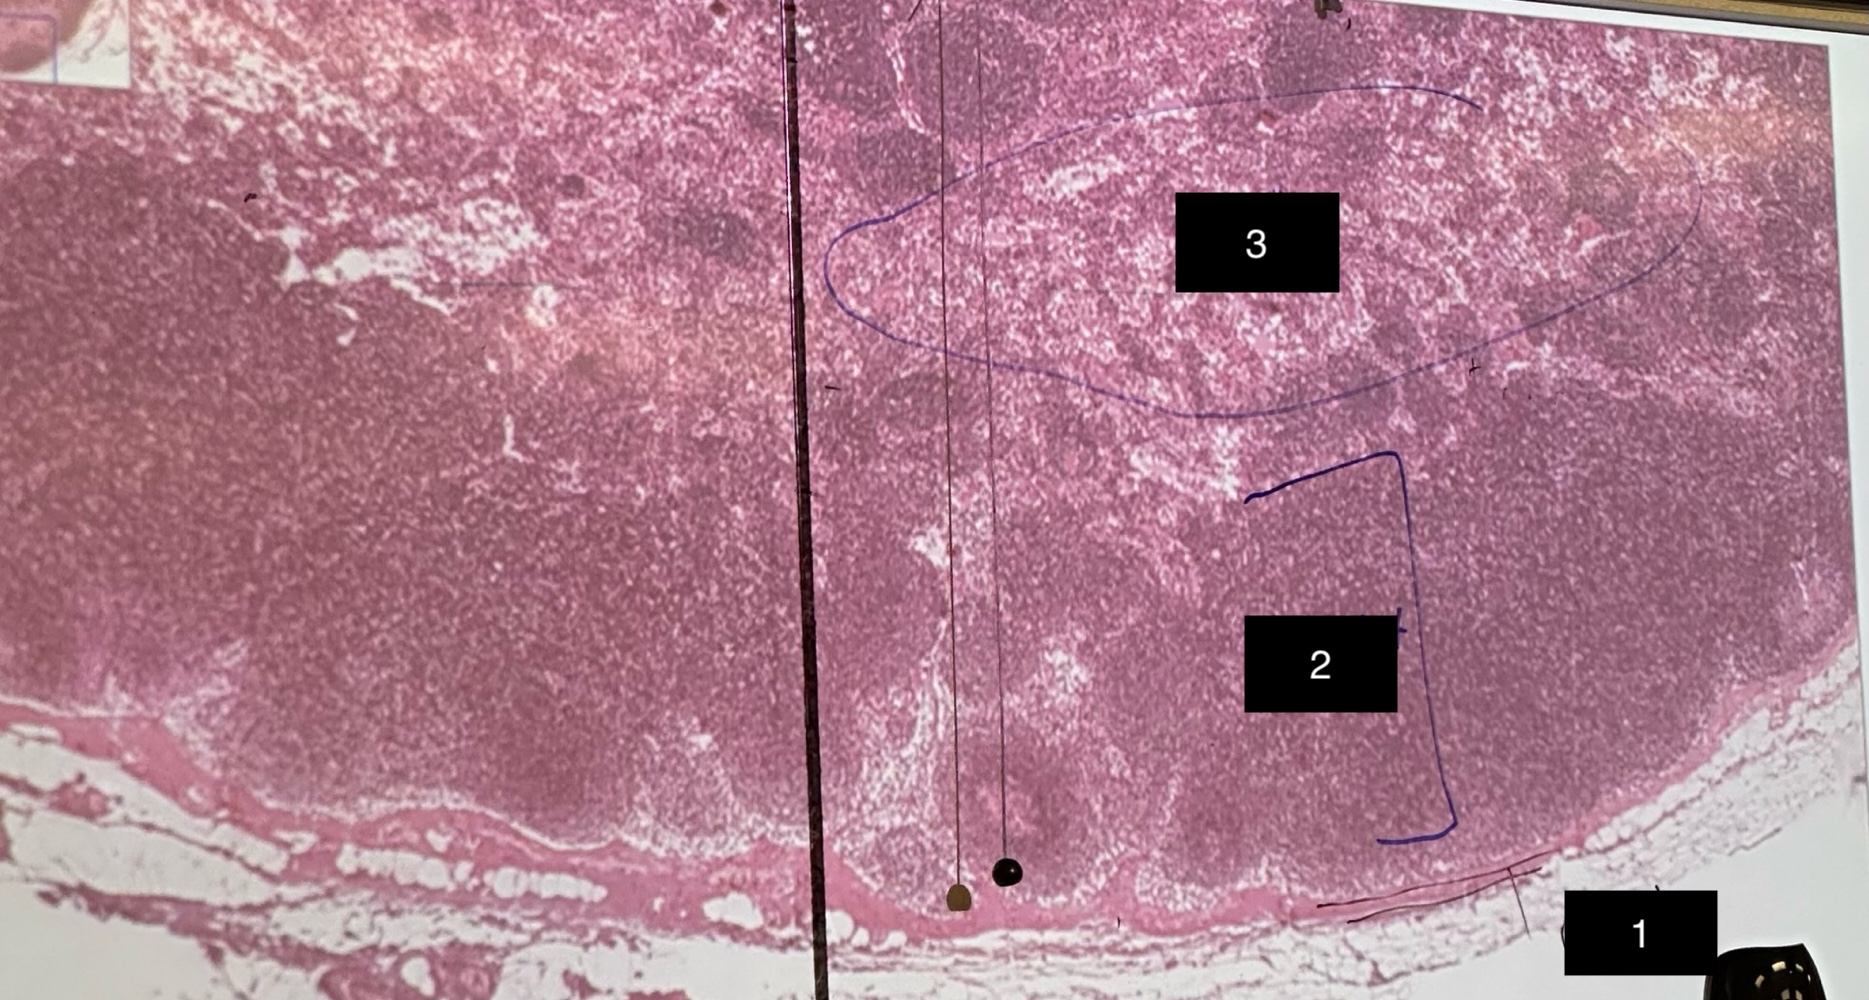

lymph node

slide

capsule

1

cortex

2

medulla

3